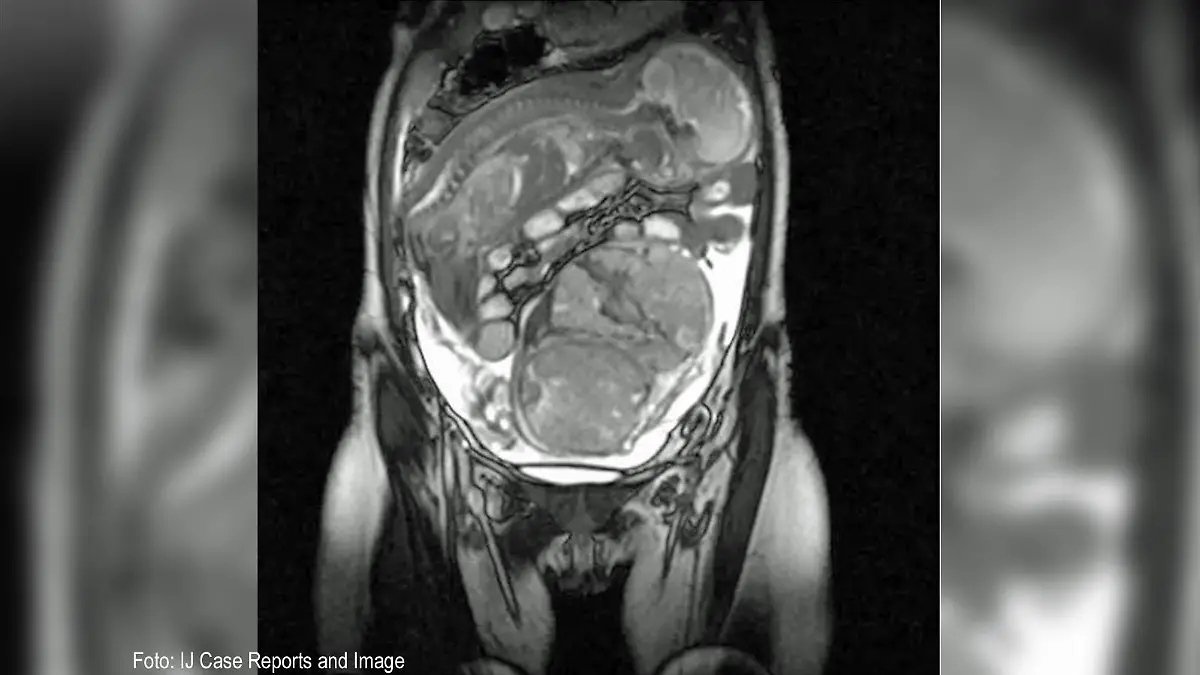

Demnach hatte die 40-jährige Frau in der 14. Schwangerschaftswoche bei sich zu Hause von einer Hebamme heimlich eine Abtreibung vornehmen lassen. Dieser Eingriff verlief fehlerhaft, so dass es zu der Komplikation kam. Medizinisch wird diese Art Schwangerschaft als "sekundäre Bauchschwangerschaft" bezeichnet.

Dort wurde festgestellt, dass sie ein gesundes Baby in ihrem Bauch hatte, dass nach dem Riss der Gebärmutter in der intakten Fruchtblase überlebt hatte. Um Mutter und Kind nicht weiteren Gefahren auszusetzen, operierte ein fünfköpfiges Team die Frau und holte das kleine Mädchen auf die Welt. Es wog 800 Gramm. Obwohl sie nicht in der Gebärmutter herangewachsen war, sei sie gesund gewesen, so die „Sun“ weiter.